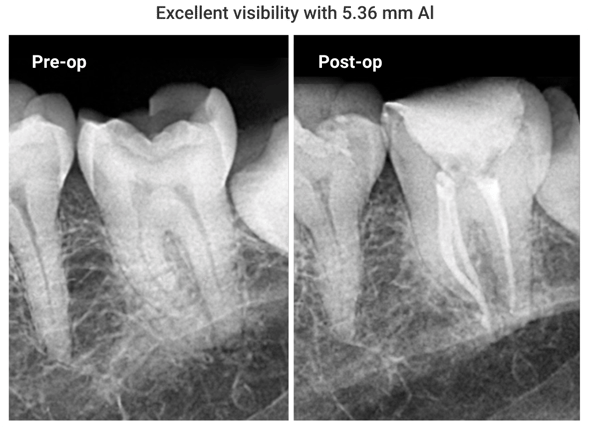

Excellent Radiopacity

The highly radiopaque and hydrophilic sealer provides tight

adhesion to both dentin and gutta percha points.

radiopacity@2x